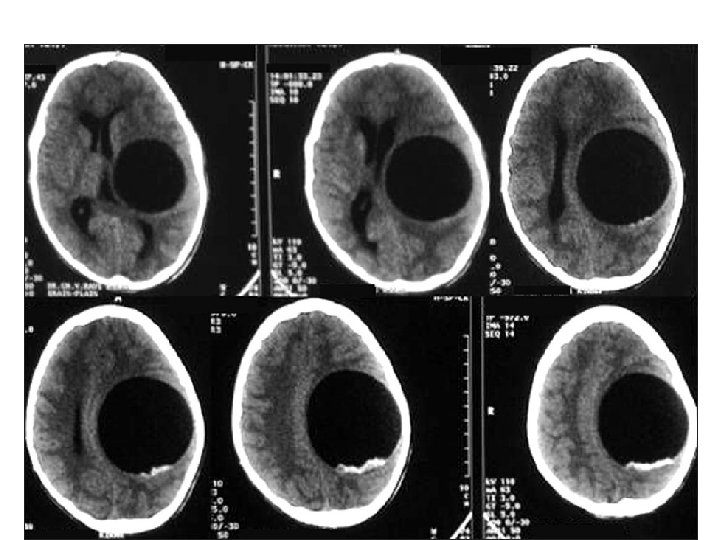

Diagnosis • large non enhancing vesicle that is well demarcated from the surrounding brain parenchyma. • Some lesions may be calcified. • epidural cysts have a biconvex shape or a multilocular appearance and may be associated with bone erosion.

Pathology • E. granulsus cysts are large, spherical, and well demarcated from surrounding tissue. • within the CNS, these cysts may be located in the brain parenchyma, ventricular system, subarachnoid space, epidural space, orbits, and both the epidural and subarachnoid spaces in the spinal canal.

CYSTIC HYDATID DISEASE OF THE BRAIN • Dowling's technique: hydrostatic expulsion of the entire cyst by irrigation of saline solution between the lesion and the surrounding nervous tissue. • The aim of this technique is to remove the cyst without damaging its walls.